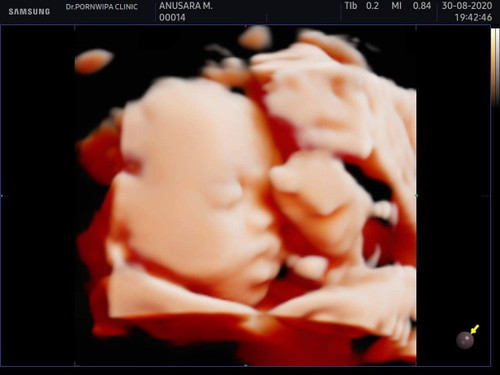

อัลตร้าซาวด์ตอน27week น้องหนัก1100กรัม ลูกคุณหนักเท่าไหร่ค่ะ